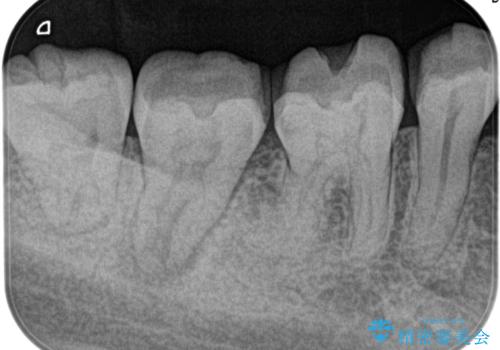

定期検診にて膿の出口を見つけた。精密根管治療

- 定期検診にて膿の出口を見つけたことを主訴に来院されました。

検査の結果、診断を歯髄壊死、症候性根尖性歯周炎とし抜髄を行っております。

根管充填はCWCTにて行なっています。